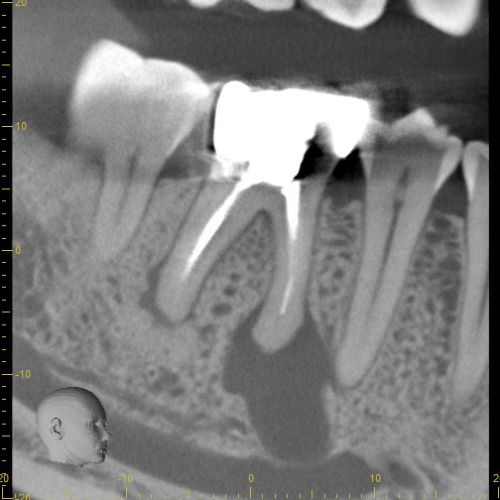

Case 7

These images are from a 3D scan and show how important is a correct diagnosis. The pre-treatment image on the left shows what looks like two teeth with infections, but thorough testing showed that only one tooth needed treatment. The right image shows complete healing--around both teeth-- one year later. A careful diagnosis resulted in saving the adjacent tooth from unneeded treatment.